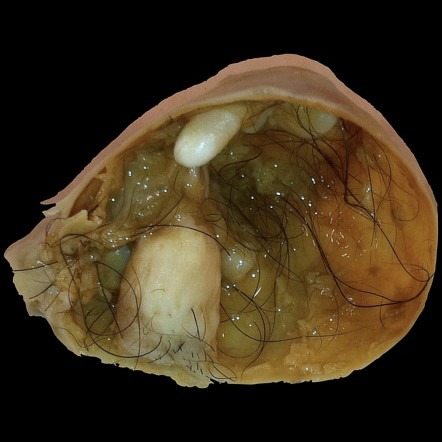

而這三種胚層會在胚胎發育時期,往他們應該走的道路前進,尤其在胚胎發育期,這些生殖細胞經由卵黃囊(yolk sac)、腸繫膜,最後降至骨盆腔或陰囊而形成卵巢或睪丸,但有些突變的生殖細胞卻迷途而不知返,隨意亂走,甚至會跨越身體中線,有些生殖細胞腫瘤除好發於性腺(gonad)(男童為睪丸,女童為卵巢)外,也會長在性腺外(extragonadal),今天我們聊的就是受困在某一側的卵巢內並落地生根的生殖細胞腫瘤,在女性生長的過程當中,這些迷途的細胞也緩緩成長,往往都是長大到一定程度因為各種腹部症狀而被檢查出來,我們臨床手術上最常在裡面看到的就是頭髮跟皮脂腺分泌的各種油膩物質(圖二),比較少見的情況也會看到軟骨、牙齒等組織,這類”良性”畸胎瘤我們也叫做皮樣囊腫(Dermoid cyst),因為裡面細胞的分化良好,意思就是生長有循序漸進、沒有要再繼續胡亂生長的意思,通常手術後就解決了,不太會復發,預後非常好,而且這類腫瘤都在相對較年輕的女性族群中發現,約為二十到四十歲。